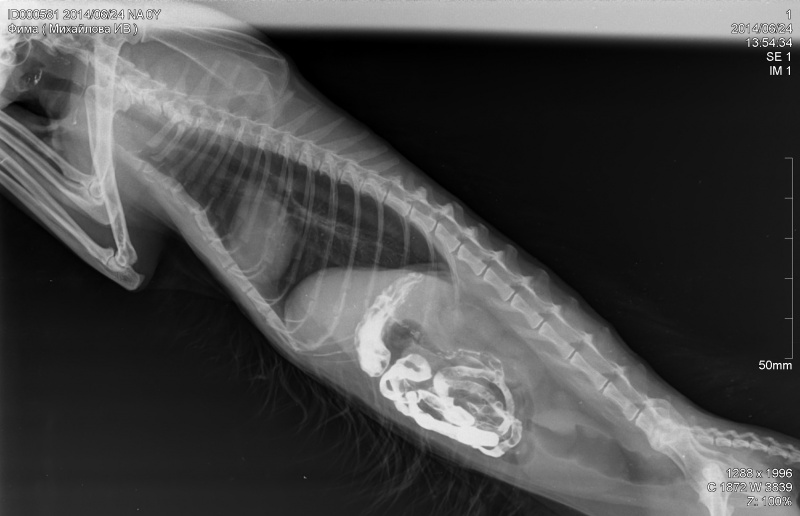

Сделали УЗИ печени и рентген ЖКТ (фото рентгена во вложении).

3. Что видно на рентгене ЖКТ кота?